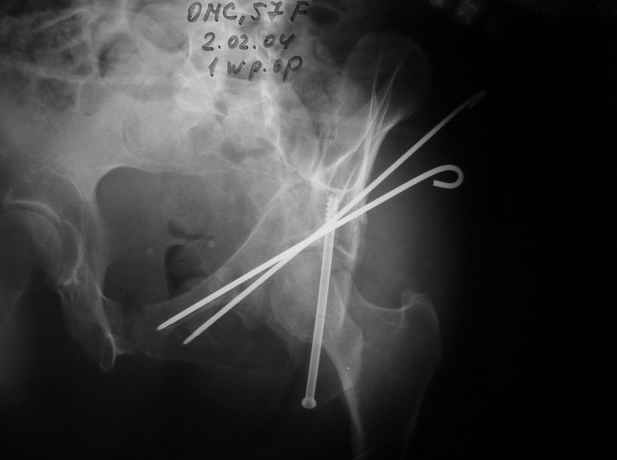

02.02.04

Anatoly F Lazarev 03 Сентябрь 2004, 22:18

Женя! Класный перелом. Отлично репонируется изнутри таза, но лучше фиксированть сзади. Классический перелом для двустороннего доступа.

Однако есть альтернатива. Репозиция из подвздошного доступа тазовыми щипцами с разнодлинными браншами или тазовым пистолетом, а фиксация задней колонны через седалищный бугор или тазрвыми винтами 4,5 или каннюлированными 6,5 или 7,3. По-моему я посылал на ортофорум такой снимок, когда жаловался на ишемический неврит седалищного нерва через сутки после операции. Не забудь про шейку бедра - мне кажется будет хорош длинный PFN любой фирмы, какую ты найдешь, а нет так UFN + miss a nail, как это здорово делают мои земляки - Ебурбуки. Пока.